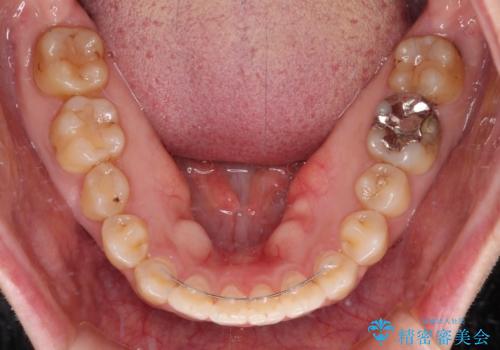

舌突出癖による開咬 舌のトレーニングを行いながら咬み合わせを改善

前歯のデコボコはもちろん気になるところですが、舌の突出癖により上下前歯が非接触となっている状態でした。

上下前歯が非接触である開咬は、インビザラインによる治療がお勧めではありますが、しっかりと使う自信がないとのことで、ワイヤー装置にて治療を行うこととしました。

デコボコはあっという間に改善されましたが、開咬の改善に時間がかかりました。

舌の突出癖改善のトレーニングをしっかりと行っていただき、上下前歯が接触する咬み合わせを達成することができました。